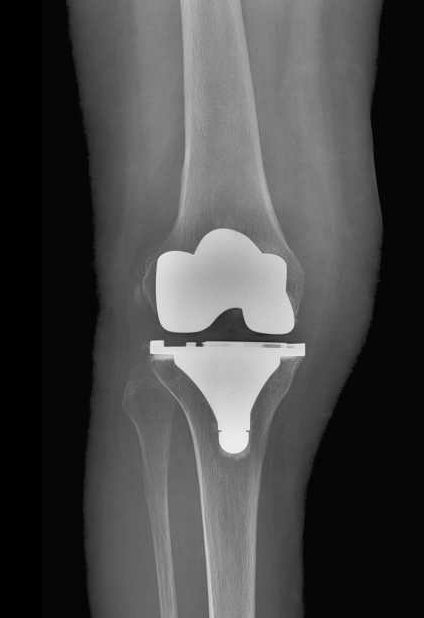

Les composants d'une Prothèse Totale de Genou

Cette intervention consiste à remplacer l’articulation du genou par des composants artificiels qui reproduisent l’anatomie initiale du genou. Le type d’implant doit être adapté à chaque cas particulier, en ce qui concerne sa forme, sa taille, la nature des matériaux entrant dans sa composition, son revêtement extérieur et la technique chirurgicale à employer.

Généralement, une prothèse de genou se divise en trois parties : un insert fémoral, une embase tibiale surmontée d’un polyéthylène et un resurfaçage de la rotule par un polyéthylène. Les composants sont le plus souvent fixés par du ciment.

La prothèse que nous mettons en place est un implant en alliage CrCoMo (implant fémoral) et titanium (implant tibial).